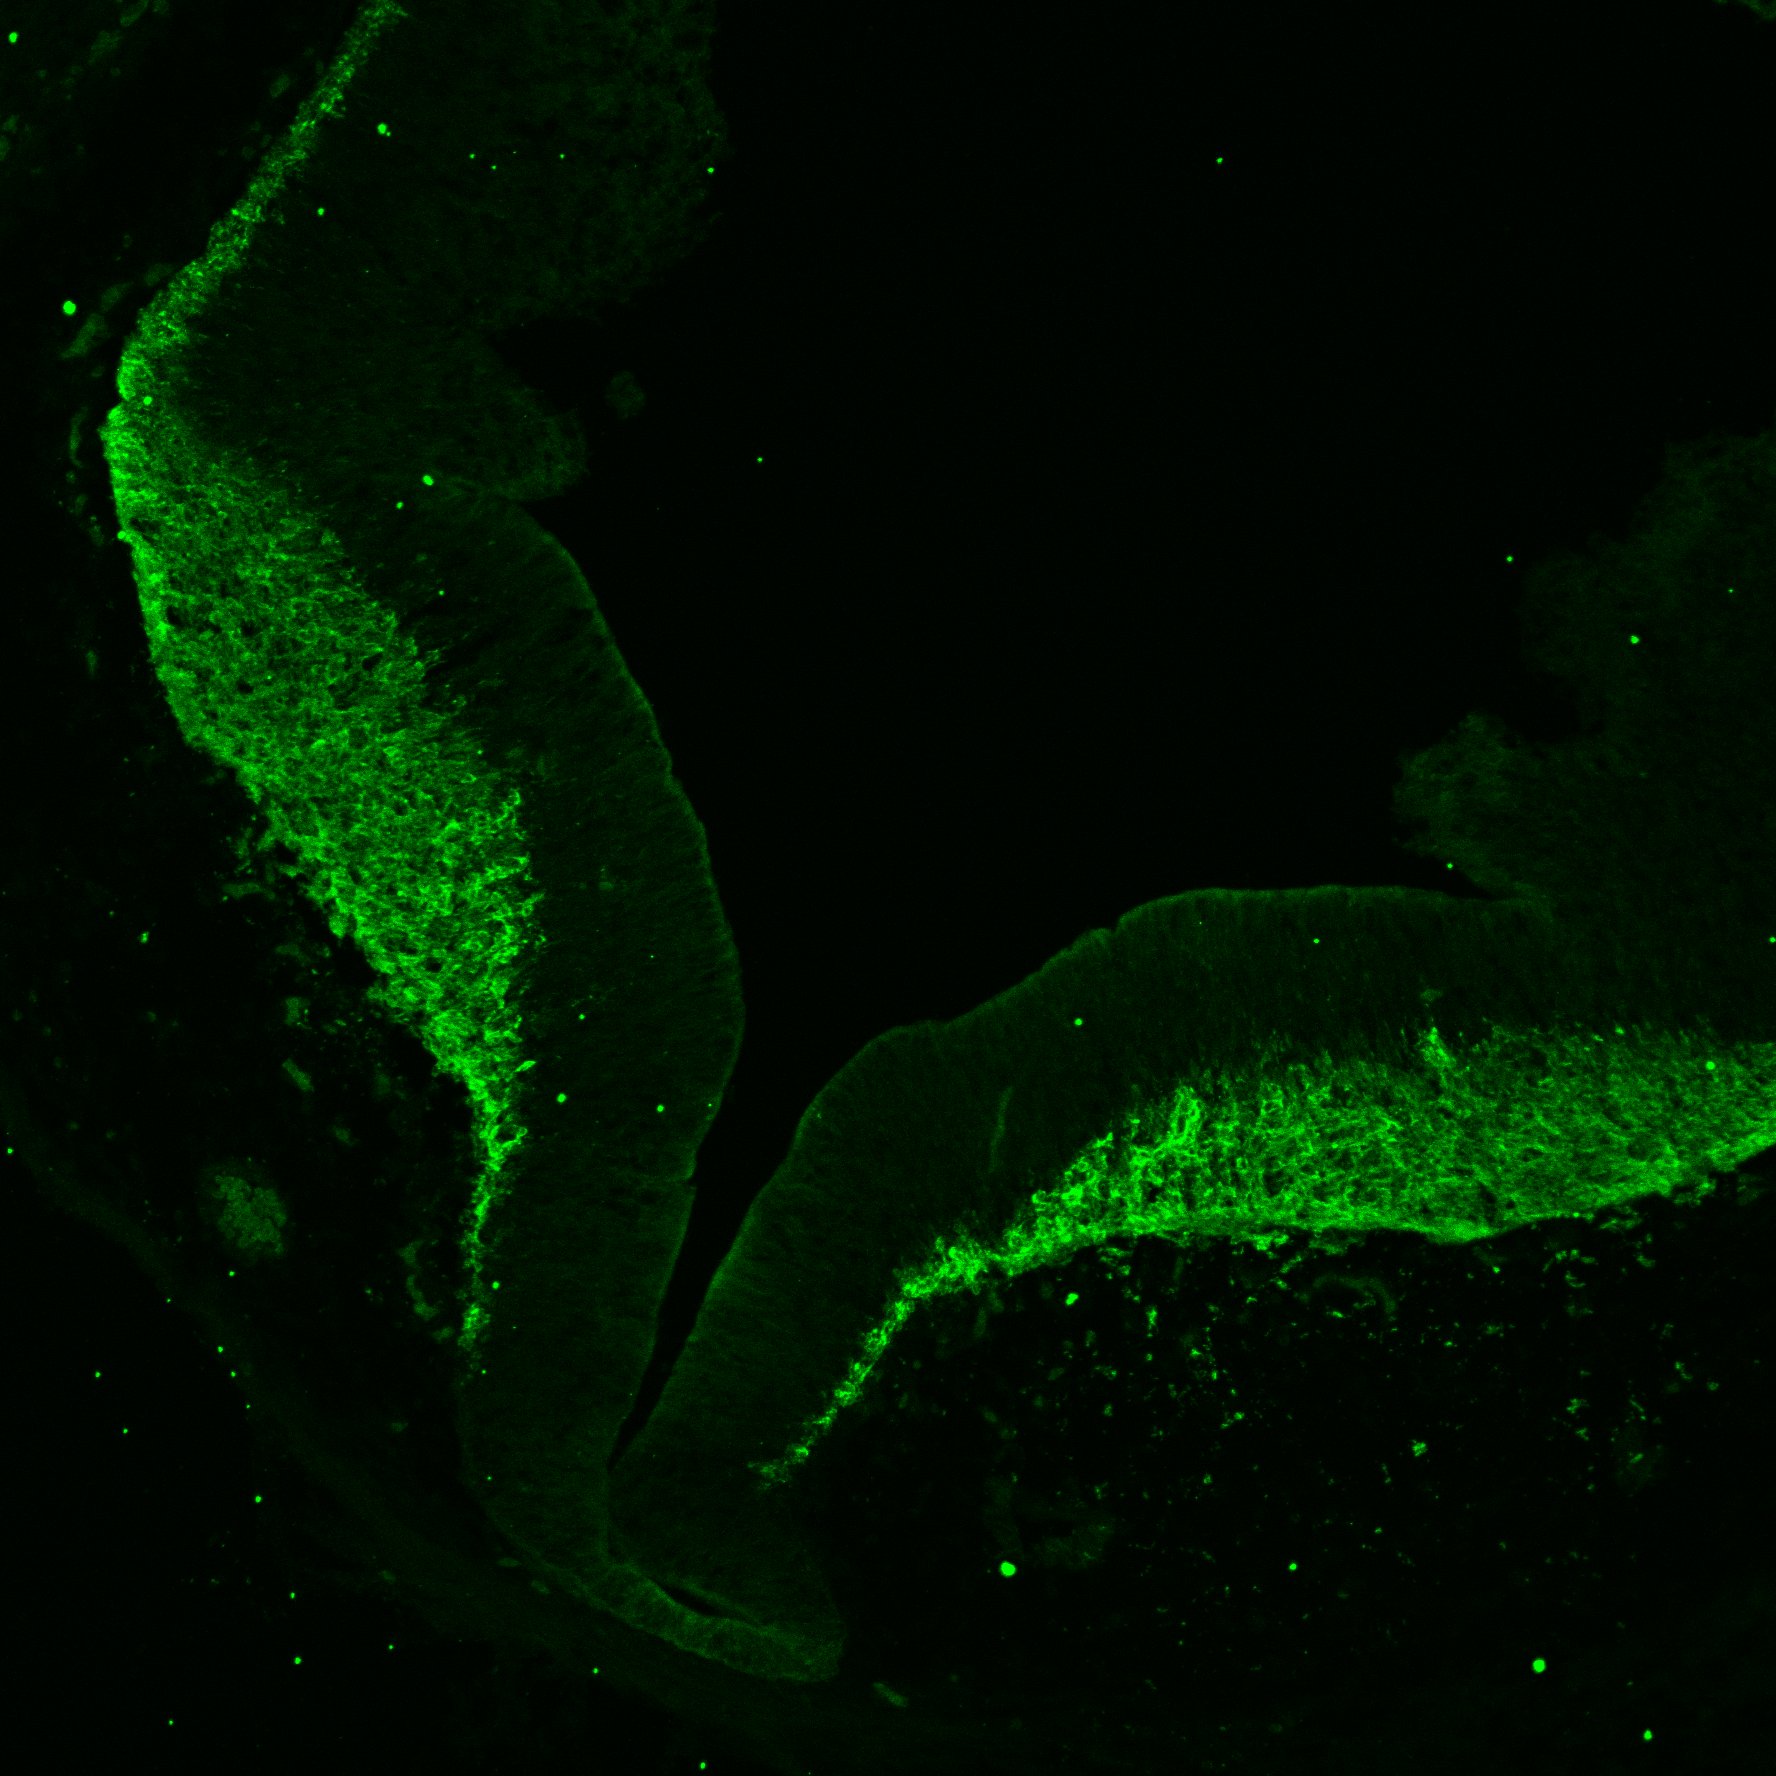

DAPI

17PCW human midbrain

MAP2

TH

Merged